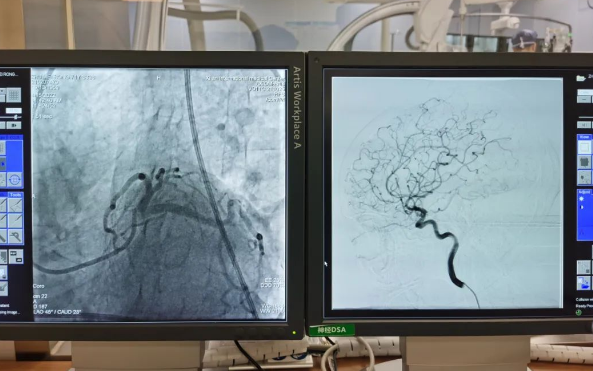

術(shù)前準備就緒后,心內(nèi)二病區(qū)曾廣偉主任、高釗副主任醫(yī)師、神外科陸丹副主任醫(yī)師共同為患者行腦血管造影術(shù) 冠狀造影術(shù)。術(shù)后,朱奶奶恢復(fù)良好。